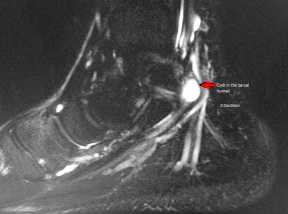

![3]()

Рис 3. МР-признаки наличия жидкостного ганглия, оказывающего патологическое давление на большеберцовый нерв.